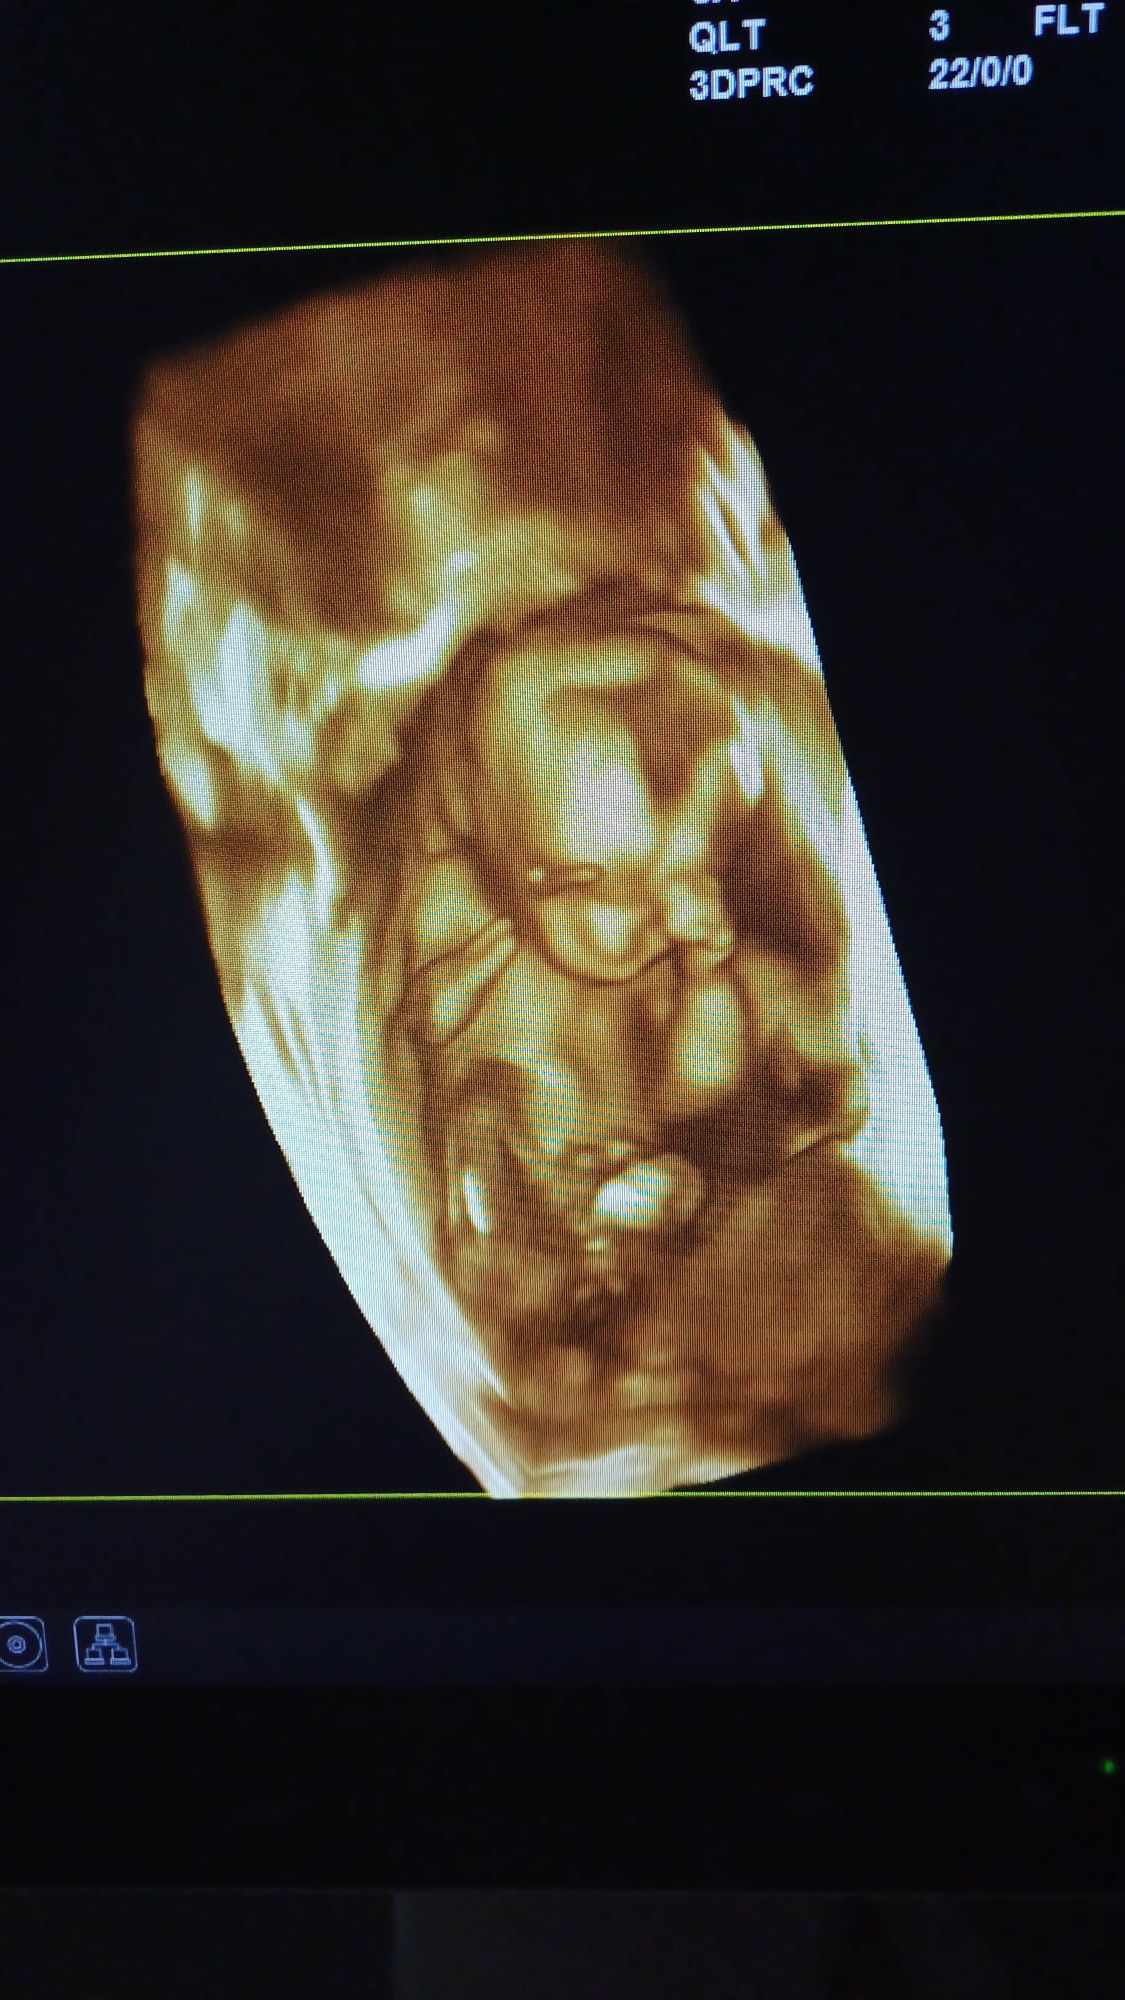

Pozrite si fotky z nášho moderného pracovného prostredia

Naša gynekologická ambulancia je vybavená modernou technikou a poskytuje pacientkom príjemné a komfortné prostredie pre všetky druhy vyšetrení a konzultácií.